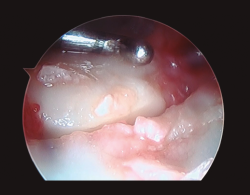

Figura 4. Desde el portal de visión radiocarpiano 3-4 se explora con el instrumental en el portal 6R el complejo del fibrocartílago triangular, observando pérdida de tensión del mismo.

- La pérdida de tensión del CFCT (signo del “trampolín”) con posibilidad de introducir el instrumental artroscópico por debajo del mismo (prueba del “gancho”)(26,27)(Figura 4). De acuerdo con la clasificación de Palmer(24), estas lesiones se trataron de la siguiente manera: tanto las lesiones de tipo IA como ID se trataron mediante un desbridamiento simple con sinoviotomo de 2,5 mm(26,27,28). En el caso de las lesiones de tipo IB y siempre que se observó una prueba del “gancho” positiva, se realizó una reinserción mediante sutura a cápsula articular o un reanclaje a fóvea, según correspondiese en cada caso(26,27,28).